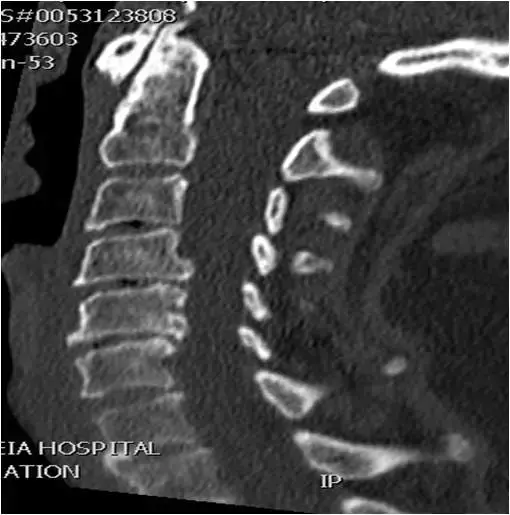

图25:颈椎的CT扫描。矢状位重建。中线部分。生理曲度变直。C5-C6和C6-C7间隙变窄,终板硬化和小的前部和后部骨赘。C6-C7椎间盘的真空征。

图26:颈椎的CT扫描。矢状位重建。中线部分。多级退行性疾病。C3-C4,C4-C5和C5-C6轻度间隙变窄。同一椎间盘的真空征。C4-C5和C5-C6后部骨赘形成。